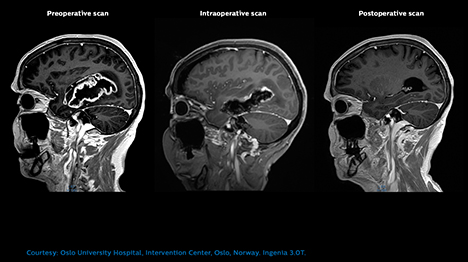

Maximizing the extent of brain tumor resection during initial neurosurgery can make a critical difference to lowering recurrence and to your patient’s prognosis. Intraoperative MR images help you understand the extent of tumor resection and see critical structures. This aids you counter the issue of brain shift and make timely adjustments to your operating strategy.

The clear benefit is that in cases where the MR-OR setup helps to visulize an incomplete resection, we can immediately address the issue using updated navigation data and thus avoid a second surgery. In addition, the final intra-operative MR replaces the post-operative one that we used to perform. Dr. Conor Mallucci, Neurosurgeon, Alder Hey Children’s Hospital, Liverpool, UK.